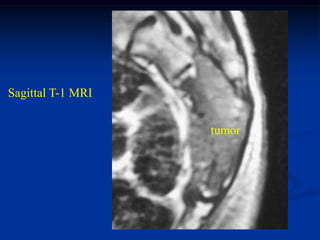

Sagittal T-1 MRI

shows recurrent tumor

above ankle

tumor